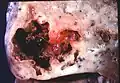

Lung abscess is a type of liquefactive necrosis of the lung tissue and formation of cavities (more than 2 cm)[1] containing necrotic debris or fluid caused by microbial infection.

This pus-filled cavity is often caused by aspiration, which may occur during anesthesia, sedation, or unconsciousness from injury. Alcoholism is the most common condition predisposing to lung abscesses.

Lung abscess is considered primary (60%[2]) when it results from existing lung parenchymal process and is termed secondary when it complicates another process e.g. vascular emboli or follows rupture of extrapulmonary abscess into lung.